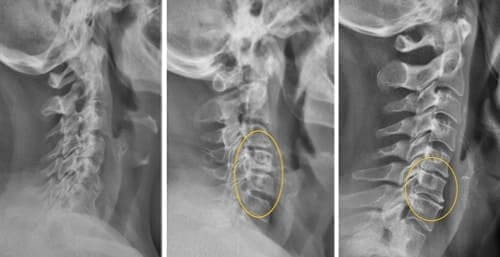

— Apakah Anda benar-benar berpikir bahwa pijat atau analgesik dapat mencegah kerusakan sendi dan tulang rawan? Itu adalah kesalahpahaman besar. Obat-obatan dari apotek tidak dapat meregenerasi jaringan, sementara bahan kimia yang terkandung di dalamnya justru merusak hati dan ginjal seiring waktu. Tubuh tidak dapat selamanya menanggung beban racun ini, dan alih-alih menyelesaikan masalah, Anda justru meracuni diri sendiri! Hal ini terutama berlaku untuk tulang belakang. Semua sendi mengalami keausan, tetapi pada tulang belakang, kurangnya ujung saraf dapat menyembunyikan perubahan yang berbahaya. Kompresi saraf skiatik akibat hernia adalah proses yang menyakitkan, awalnya menyebabkan nyeri ringan di punggung bawah, lalu menjalar ke kaki, menyebabkan kesemutan, mati rasa, dan akhirnya hilangnya fungsi kaki sepenuhnya. Kerusakan yang terus berkembang akan menyebabkan kelumpuhan pada bagian bawah tubuh, dan mengembalikan kendali atasnya menjadi hampir tidak mungkin. Lihat gambar ini. Ini adalah kondisi tulang belakang seseorang yang baru berusia 44 tahun, tetapi tampak seperti lansia. Dulu, kerusakan seperti ini hanya terjadi setelah usia 60 tahun, tetapi sekarang hal ini menjadi umum bagi mereka yang baru saja melewati usia 40 tahun. Kerusakan ini akan terus berkembang seiring bertambahnya usia, dan mengabaikannya berarti menempatkan diri dalam risiko kelumpuhan total!

Tulang belakang pasien berusia 44 tahun: semuanya dimulai dengan nyeri ringan, tetapi hanya dalam satu minggu muncul hernia, dan dalam dua minggu terjadi pergeseran tulang belakang, tekanan pada saraf, dan akhirnya—kursi roda.